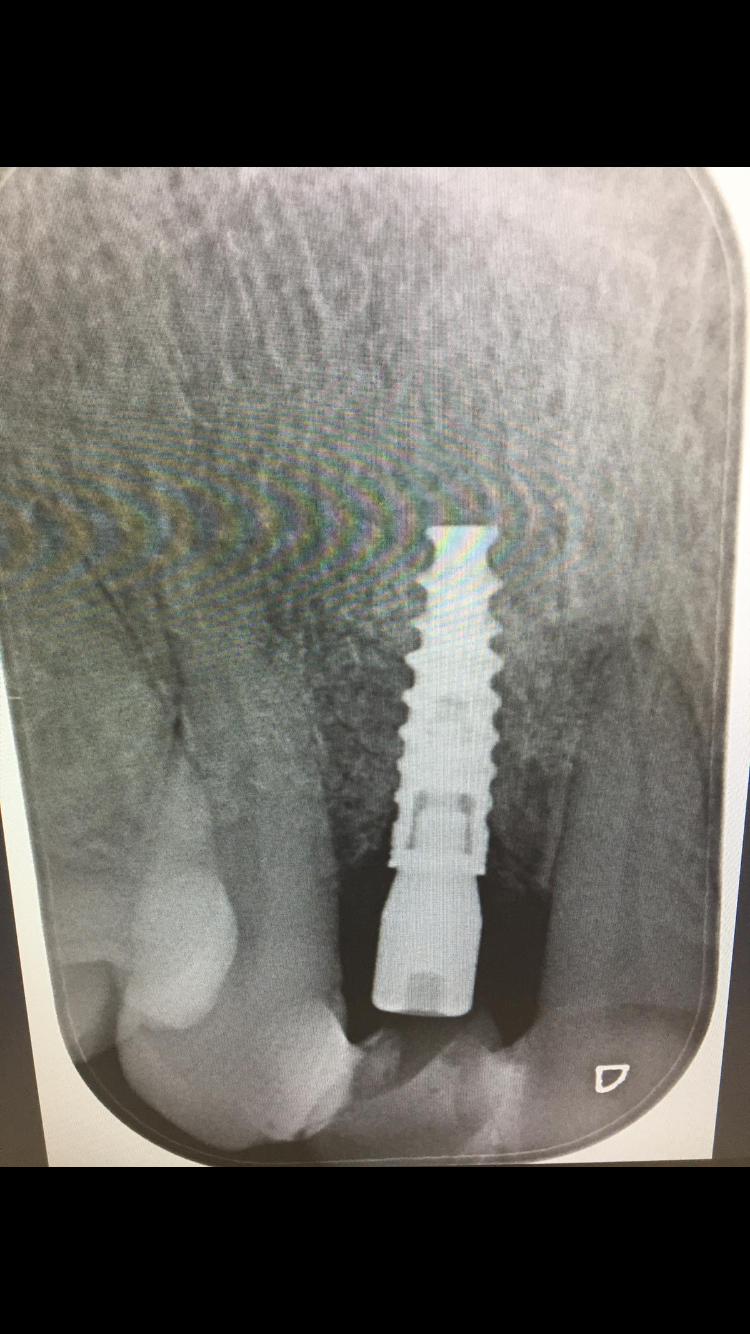

Implante conexión externa

Buenas. Me ha llegado una paciente con este implante colocado en Madrid hace 8 años aproximadamente. Me dice que la clínica está cerrada. Llevaba una corona cementoatornillada que se le [...]